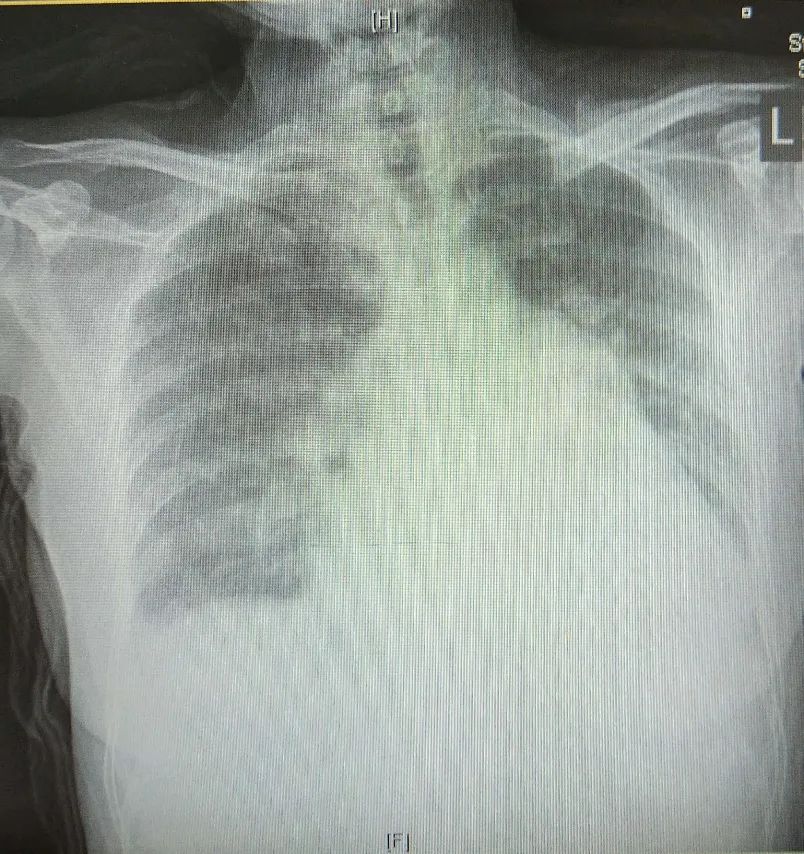

• 2021-03-29胸片:心影增大,双肺瘀血,少量胸腔积液